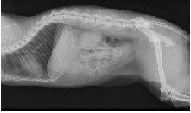

• Röntgen der Zähne, Brust - und Bauchhöhle, der Gelenke und der Wirbelsäule